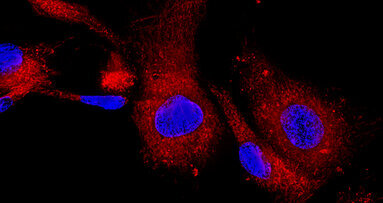

Durante lo studio, i ricercatori hanno utilizzato una matrice di collagene con particelle contenenti il DNA codificato per un fattore di crescita chiamato PDGF-B. Processo che quindi può fornire istruzioni alle cellule di produrre l’osso direttamente nell'osso esistente, consentendo inoltre alle cellule a produrre proteine che migliorano la rigenerazione ossea.

Secondo i ricercatori, gli esperimenti preliminari in laboratorio con crani in cui vi era una mancanza d’osso, quattro settimane dopo hanno mostrato un nuovo volume significativamente più alto di rigenerazione (5 mm x 2 mm) rispetto alle matrici vuote. Gli scienziati hanno affermato che il BIOPATCH ha portato ad una rigenerazione maggiore di oltre 44 volte dell'osso e dei tessuti molli nella zona interessata. Inoltre, hanno mostrato significativa proliferazione di cellule di midollo osseo umano sulla matrice di collagene caricata rispetto alle matrici vuote.